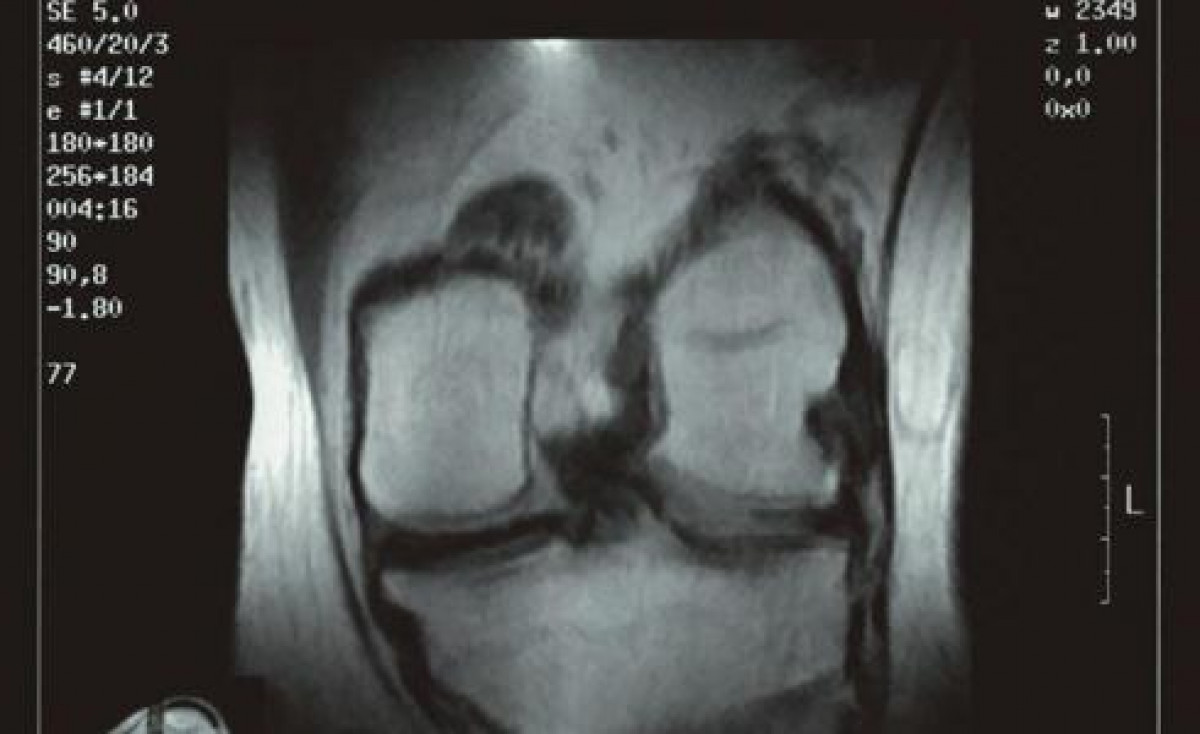

El hecho de que "claramente" la artrosis es una enfermedad femenina, sobre todo en rodilla y manos, y de que su diagnóstico se dispara en mujeres durante el climaterio lleva a pensar en una relación directa. "Cuando es una enfermedad de género se sospecha que algo tiene que ver con las hormonas, y, efectivamente, el cartílago está cargado de receptores estrogénicos, que se ven relacionados en la menopausia y, junto con la perdida de colágeno, hace que en la persona que tiene predisposición a la artrosis se agrave".

La artrosis es una enfermedad inflamatoria crónica que afecta a toda la articulación. El 80 por ciento de las mujeres menopáusicas sufre dolor articular de origen artrósico, de las que el 50 por ciento lo define como insoportable o importante. A parte del dolor, otros síntomas son la limitación de la movilidad, inflamación, crujidos en la articulación afectada y rigidez.